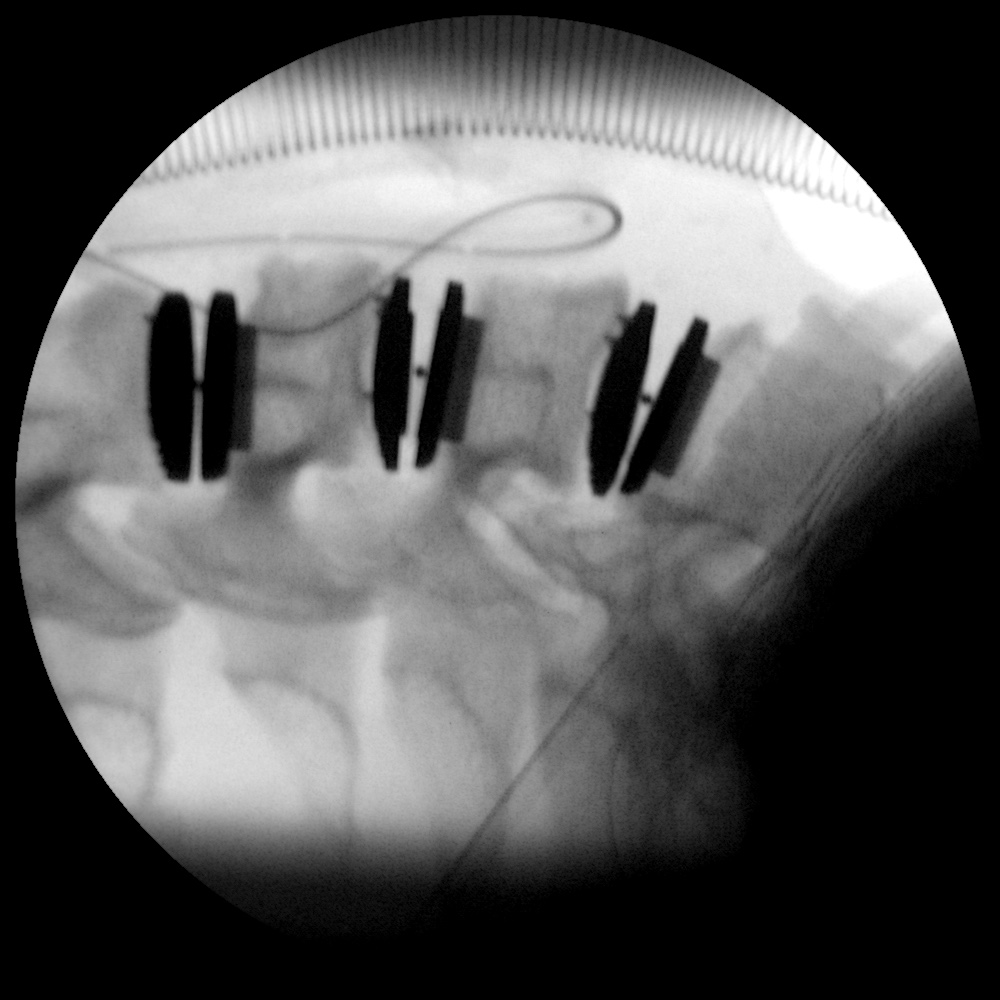

Caso clínico: endoscopia de columna multinivel L4L5 y L5S1

Los síntomas que presentaba el paciente eran dolores acentuados en las piernas, claudicación a la marcha y calambres y hormigueos en las piernas.

Durante la intervención quirúrgica, se abordarán los dos niveles mediante la técnica de endoscopia de columna.